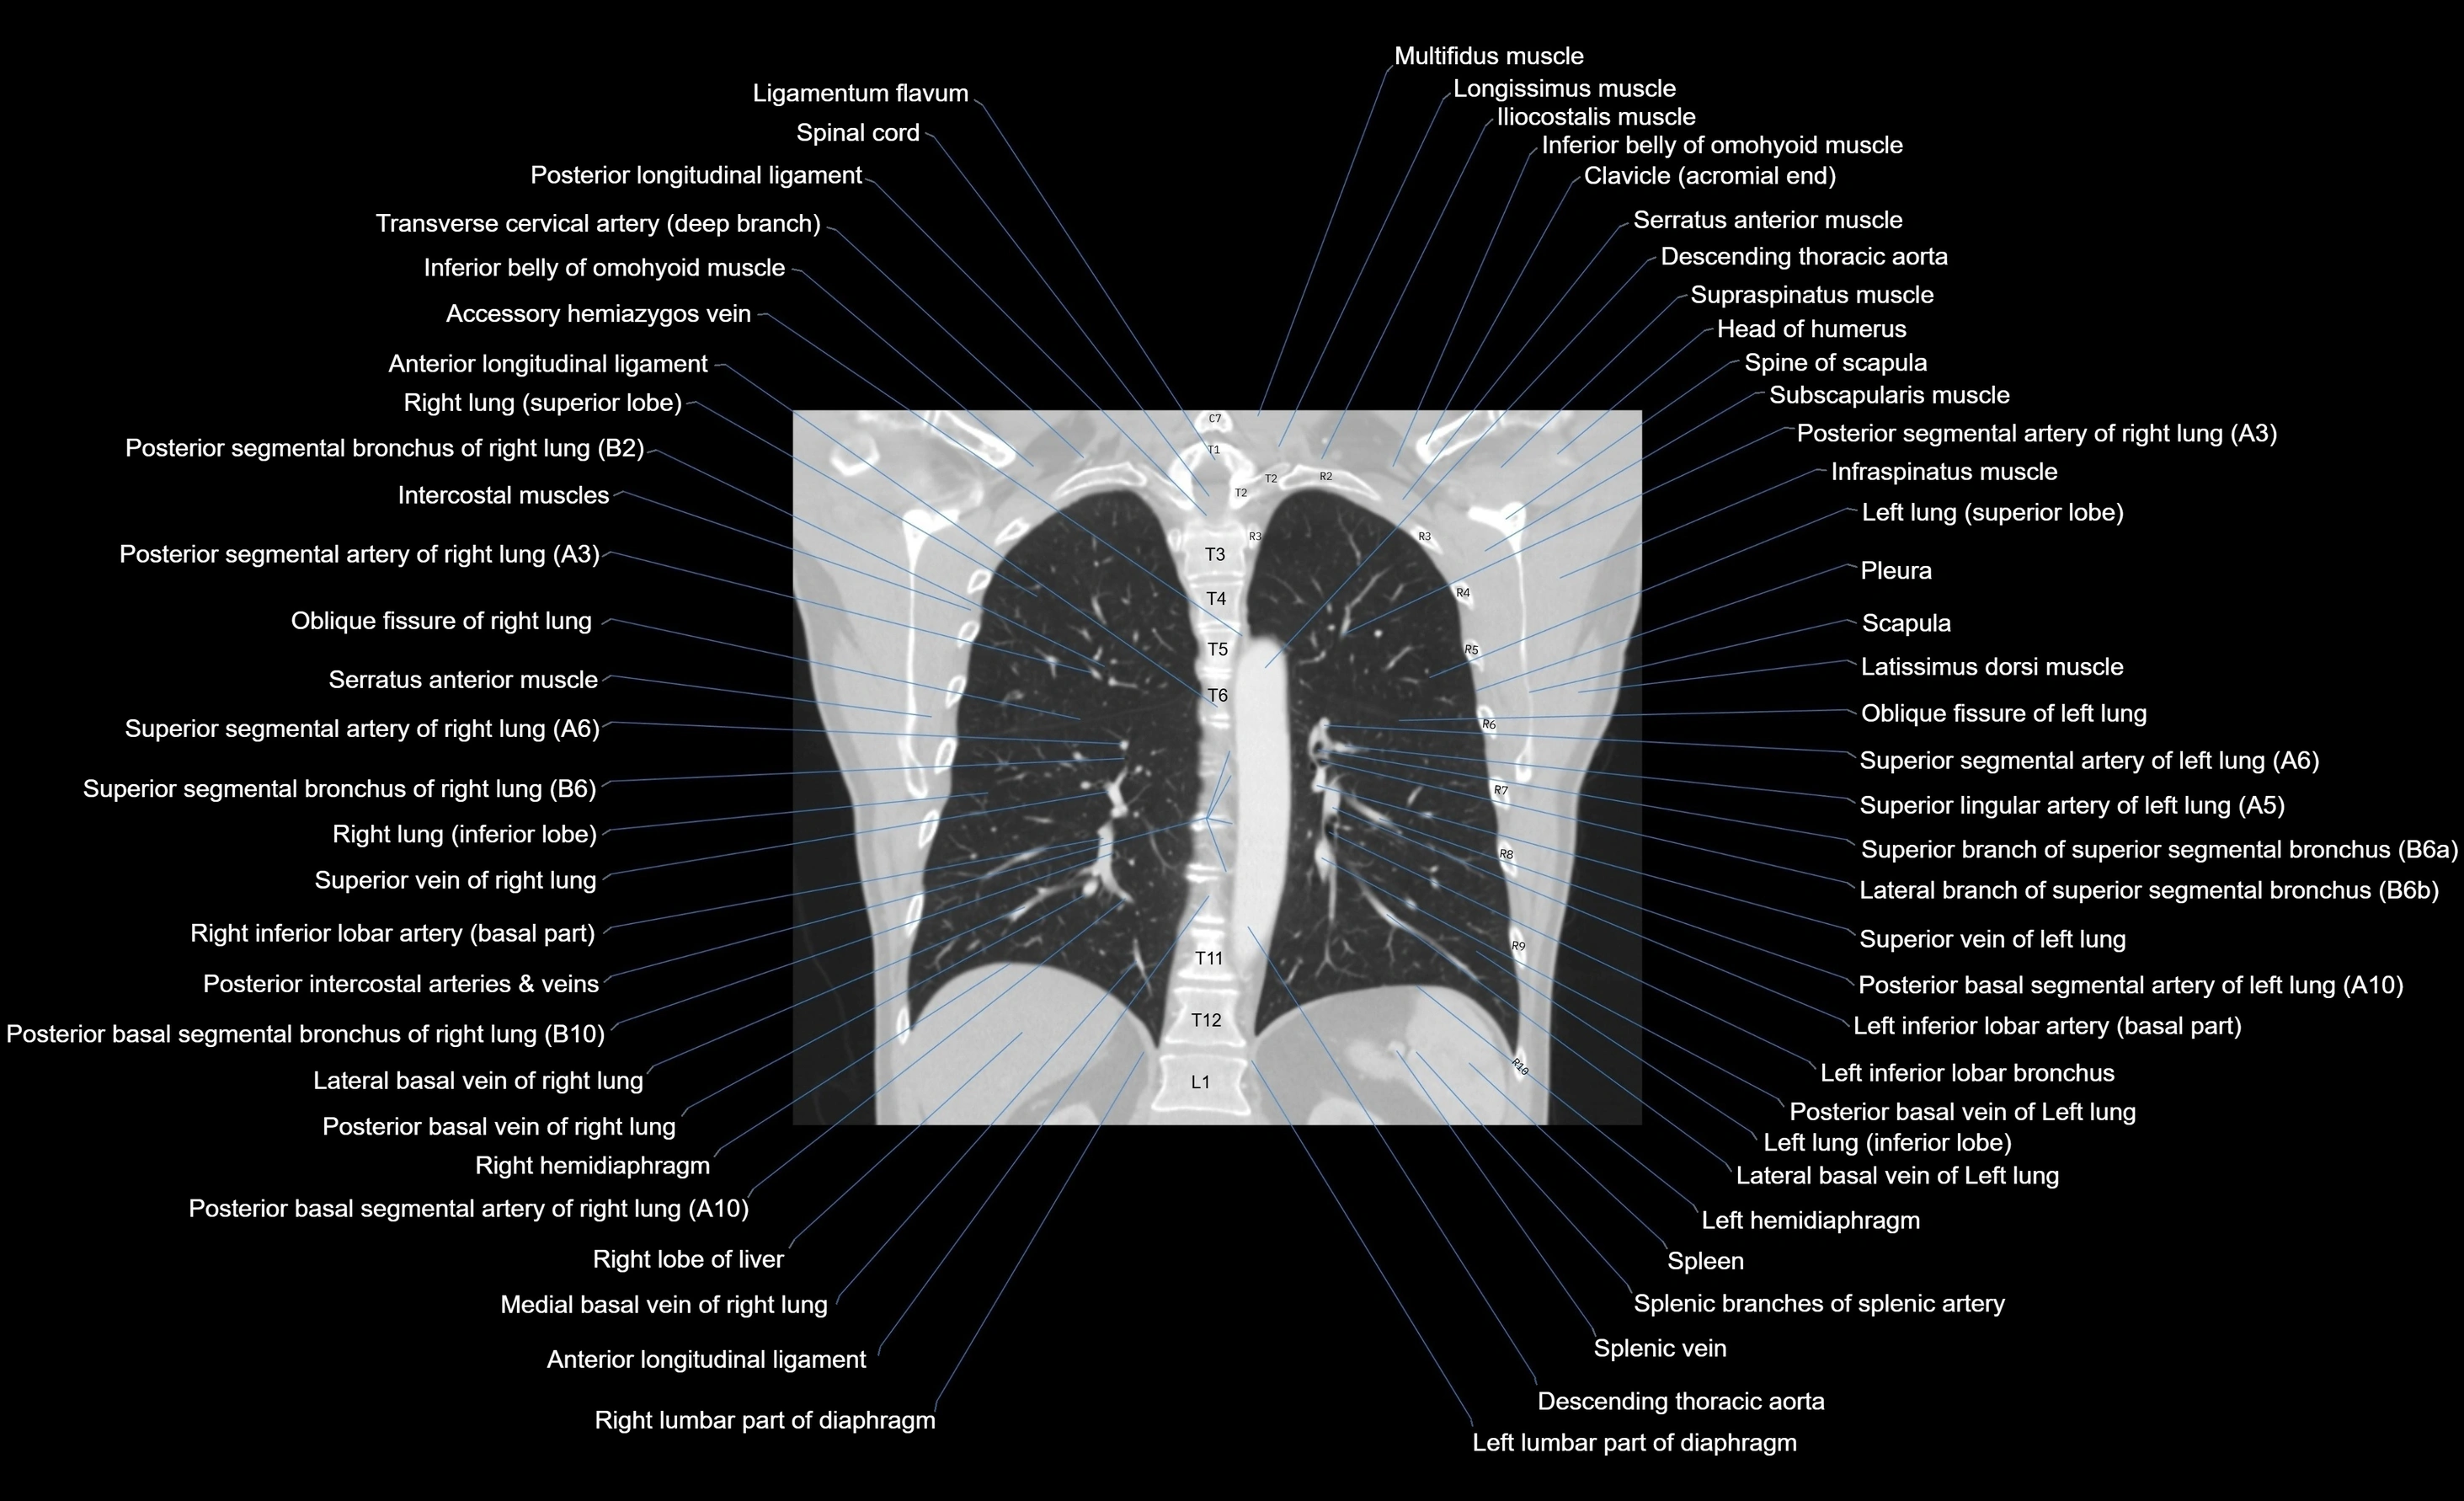

- Descending thoracic aorta

- Inferior lobe of left lung

- Inferior lobe of right lung

- Left hemidiaphragm

- Oblique fissure of left lung

- Oblique fissure of right lung

- Posterior basal segmental artery of left lung

- Posterior basal segmental artery of right lung

- Posterior basal segmental bronchus of left lung (B10)

- Posterior basal segmental bronchus of right lung (B10)

- Posterior basal vein of left lung

- Posterior basal vein of right lung

- Spleen

- Splenic artery

- Splenic branches of splenic artery

- Splenic vein